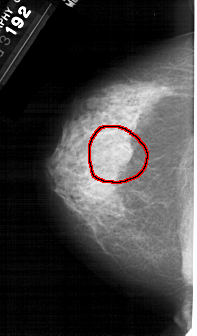

A_1396_1.RIGHT_MLO

RIGHT_MLO LINES 5491 PIXELS_PER_LINE 3301 BITS_PER_PIXEL 12 RESOLUTION 43.5 NON_OVERLAY

FILE: A_1396_1.LEFT_CC.OVERLAY

TOTAL_ABNORMALITIES 1

ABNORMALITY 1

LESION_TYPE MASS SHAPE ROUND MARGINS OBSCURED

ASSESSMENT 4

SUBTLETY 3

PATHOLOGY BENIGN

TOTAL_OUTLINES 1

BOUNDARY